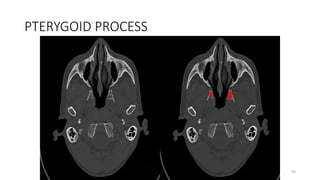

PTERYGOID PROCESS